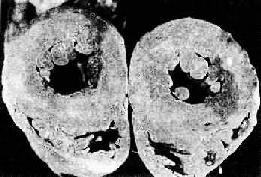

竇性停搏CT掃描2.繼發性竇性停搏